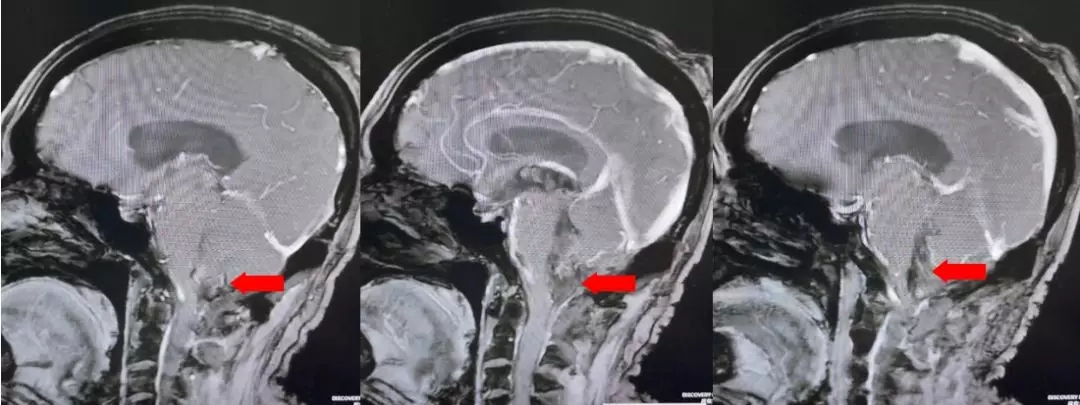

颅脑核磁T1W1成像

颅脑核磁增强扫描

颅脑核磁平扫加增强扫描:

第四脑室内见一巨大形态不规则的异常信号影,肿瘤信号不均匀,T1W1呈略低信号影,T2W1呈稍高及高信号影,增强扫描可见肿瘤不均匀明显强化。肿瘤充满整个四脑室,大小约44*37*55mm,上方接近四脑室顶部,下方至颈2脊髓平面上方,已经部分侵袭桥脑、延髓,局部边界不清,无明显间隙,脑干局部明显受压变形。肿瘤上方脑室系统扩张,出现梗阻性脑积水征象。

影像诊断:1.第四脑室内占位性病变,室管膜瘤可能性大;2.梗阻性脑积水。